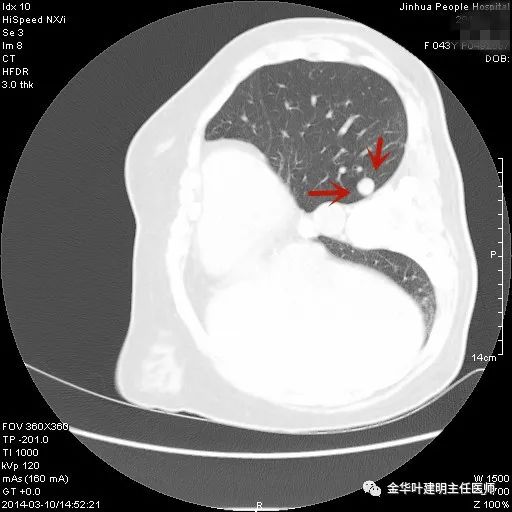

上图示典型的肺内淋巴结影像。靠近胸膜,高密度,三角形工多边形,相对比较孤立,周围没有炎性渗出或卫星灶,邻近胸膜(包括叶间胸膜)但无胸膜牵拉凹陷。